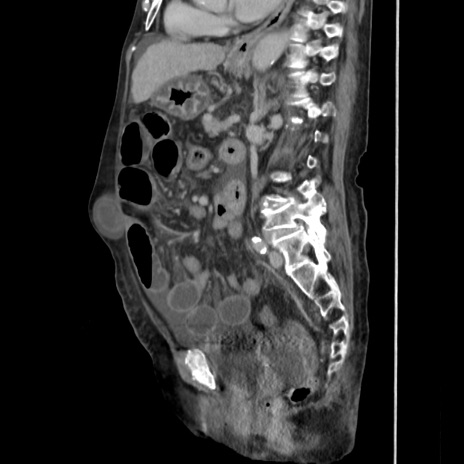

症例31(矢状断像)

【症例】80歳代 女性

【主訴】腹部膨満感

【現病歴】他院にて肝硬変にてフォロー中。1週間前から便秘、腹部膨満感、臍部腫瘤あり受診となる。

【既往歴】肝硬変

【身体所見】腹部膨隆あり、皮膚変化なし、疼痛なし。

【データ】WBC 4600、CRP 0.25